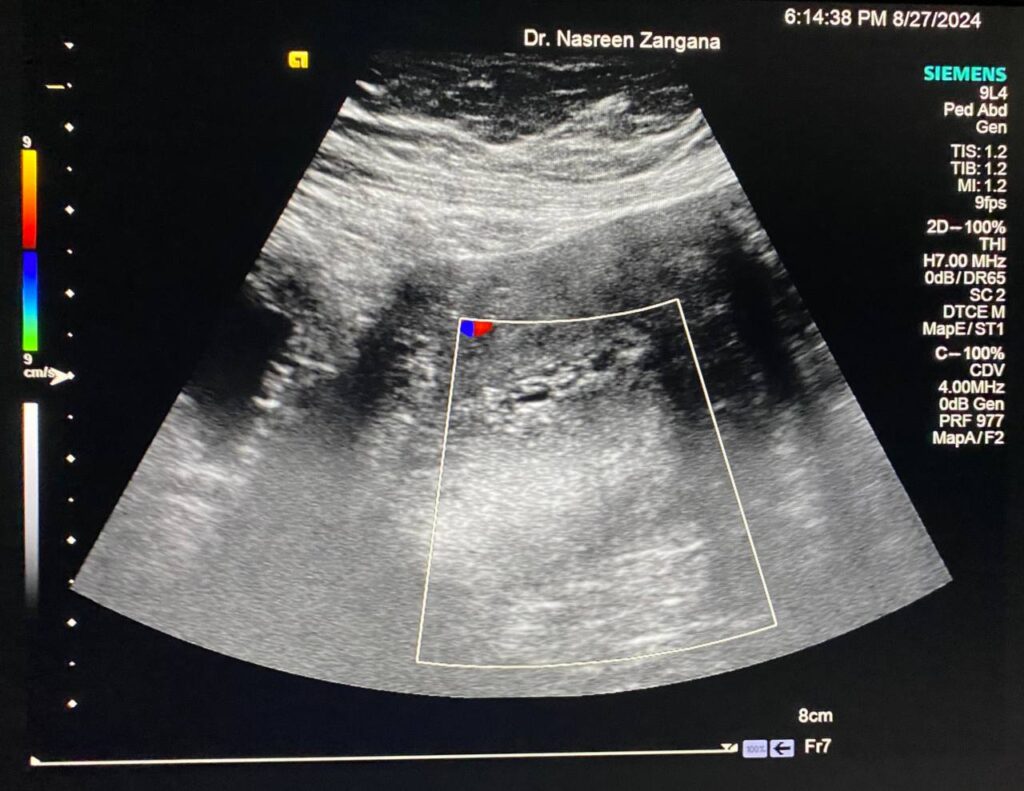

Color Doppler, Pelvis

Endometrial cavity, patient on Tamoxifen, increase endometrial thickness, cystic changes of the endometrial lining avascular in patient menapause , history of Ca breast